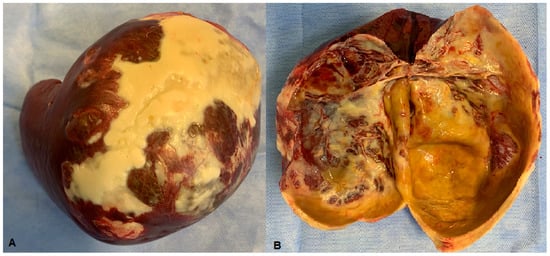

2. Case Presentation